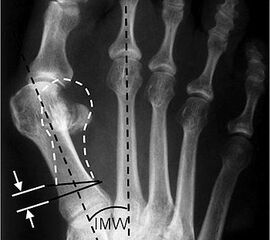

Präoperative Planung. Ziel ist es, den Metatarsalekopf auf den Sesambeinkomplex zu reponieren.

Abbildung 1

• Röntgenaufnahme des Fußes unter Belastung in d.p., schräg und seitlichem Strahlengang.

• Beurteilung des Intermetatarsalwinkels (IMA) und des distalen und proximalen Gelenkwinkels (DMAA, PMAA) (Abb. 1).

• Planung der Korrekturosteotomie: 1 mm Plattensteg korrigiert etwa 2° Intermetatarsalwinkel.

• Planung der Osteotomie mit ausreichendem Abstand vom Tarsometatarsale I Gelenk (ca. 1 cm). Vor allem bei sehr schräg angelegten Tarsometatareale I Gelenken besteht das Risiko mit den proximalen Schrauben in das Gelenk vorzudringen.